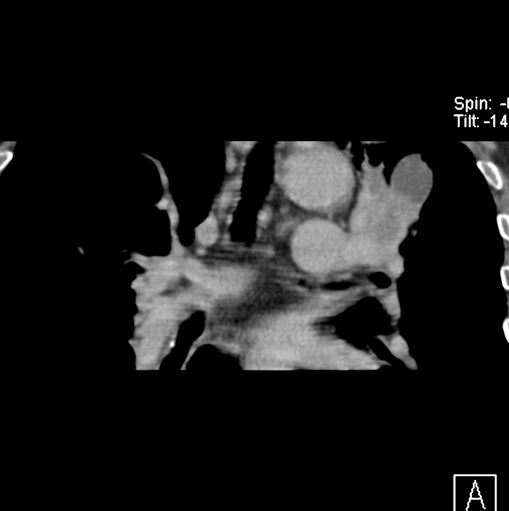

标题: CT25434:胸部CT增强扫描

男性患者 81岁 咳嗽 咳痰 咯血

肿块贴近左肺门,包绕左上肺动脉,形态不规则。肿块增强扫描中度强化。纵膈内主动脉弓左旁间隙、气管隆突前、下间隙见多枚淋巴结影。综上考虑左侧中央型肺癌可能性大。图片没有完整上传,尤其是左肺上叶支气管分支层面没有上传,因此不好判断是叶支气管中断还是段支气管中断。另外,下图红色部分所示是“黏液支气管征”吗?